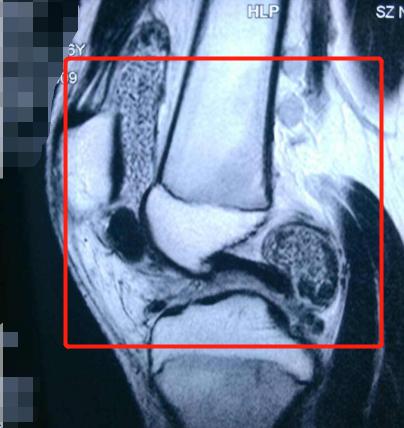

可见关节软组织病变